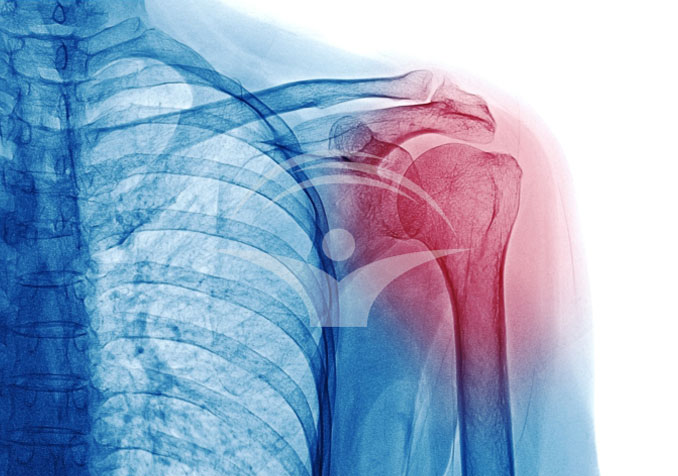

Leziunea Bankart duce la instabilitatea articulatiei

In general, leziunea Bankart este asociata cu un umar dislocat, iar primele doua simptome sunt durerea si instabilitatea articulatiei. De multe ori, durerea chiar creste in intensitate. Ce este mai exact leziunea Bankart si cum poate fi tratata? Aflati din acest material.

Leziunea Bankart este o afectiune comuna care apare in articulatia umarului si este asociata in special cu luxatia anterioara recurenta a umarului. Denumirea afectiunii provine de la numele chirurgului britanic care a descris pentru prima data aceasta leziune, in anul 1923, si anume Arthur Sydney Blundell Bankart.

Articulatia umarului este complexa si are un rol foarte important, acela de a ne permite sa efectuam diferite activitati, de la cele mai simple, la cele mai complexe. Articulatia este compusa din humerus (osul bratului) si glena, parte a omoplatului (scapula).

In timpul unei luxatii anterioare a umarului, capul osului humerus poate sa iasa din articulatia glenoida (cavitatea umarului). Aceasta miscare fortata poate duce la ruperea sau lezarea ligamentelor si a tesuturilor moi care mentin articulatia in pozitie.

Stabilitatea articulatiei este data de lambrum. Atunci cand labrumul sufera o leziune sau se rupe in urma unui traumatism, atrage dupa sine si instabilitatrea articulatiei, iar pacientul nu mai poate afectua miscarile corect sau le poate efectua cu mare greutate.